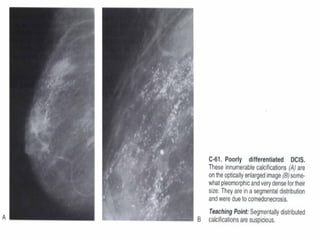

Suspicious morphology

Fine pleomorphic (BI-RADS 4C)

Fine linear or fine-linear branching (BI-RADS 4C)

Thin, linear irregular calcifications, may be discontinuous, occasionally branching

forms can be seen, usually < 0,5 mm.

Distribution of calcifications

The arrangement of calcifications, the distribution, is at least as important as

morphology.

These descriptors are arranged according to the risk of malignancy:

Diffuse: distributed randomly throughout the breast.

Regional: occupying a large portion of breast tissue > 2 cm greatest dimension

Grouped (historically cluster): few calcifications occupying a small portion of breast

tissue: lower limit 5 calcifications within 1 cm and upper limit a larger number of

calcifications within 2 cm.

Linear: arranged in a line, which suggests deposits in a duct.

Segmental: suggests deposits in a duct or ducts and their branches.

The 2013 edition refines the upper limit in size for grouped distribution as 2 cm

(historically 1 cm) while retaining > 2 cm as the lower limit for regional distribution.